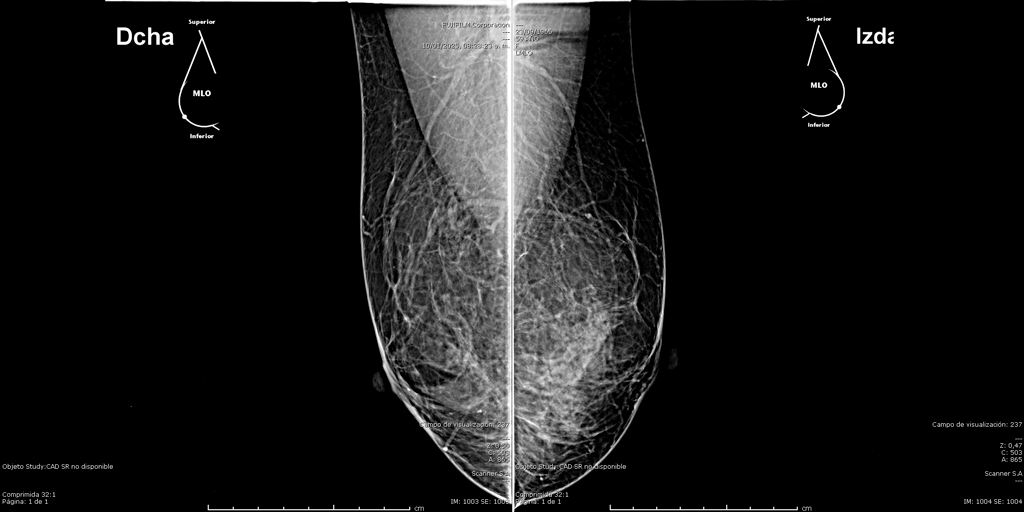

Mamografía Digital

La mamografía es un estudio de diagnóstico por imagen que utiliza bajas dosis de rayos X para obtener imágenes detalladas del tejido mamario. Es una herramienta fundamental para la detección temprana del cáncer de mama y otras patologías mamarias, incluso antes de que sean evidentes al tacto o generen síntomas. Su uso regular en controles preventivos permite salvar vidas al facilitar diagnósticos oportunos y tratamientos más efectivos.

En SCANNER S.A, nuestros equipos digitalizados permiten detectar cambios mínimos en el tejido mamario con alta claridad, permitiendo asi tener un diagnostico preciso y entregar unos resultados reales a nuestros pacientes.